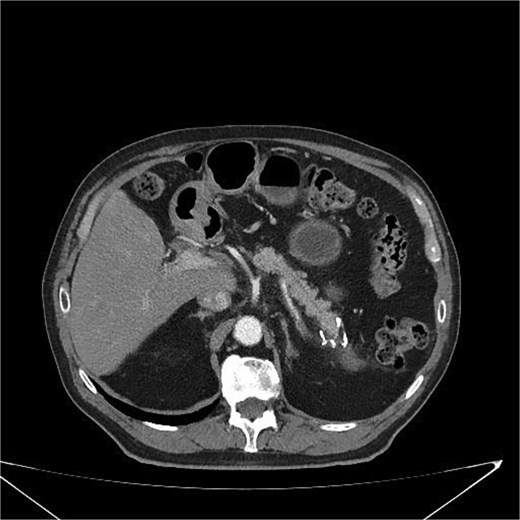

At 3 and 6 months postoperatively, CT showed no recurrence or metastases (Fig. 6). The patient remained asymptomatic with improved quality of life, including weight stabilization and resolution of abdominal pain.

Postoperative CT scan showing surgical clips in the pancreatic tail region and a hypodense nodular lesion with lipomatous characteristics, measuring 2.1 cm, adjacent to the surgical site. No evidence of recurrence or complications is observed.